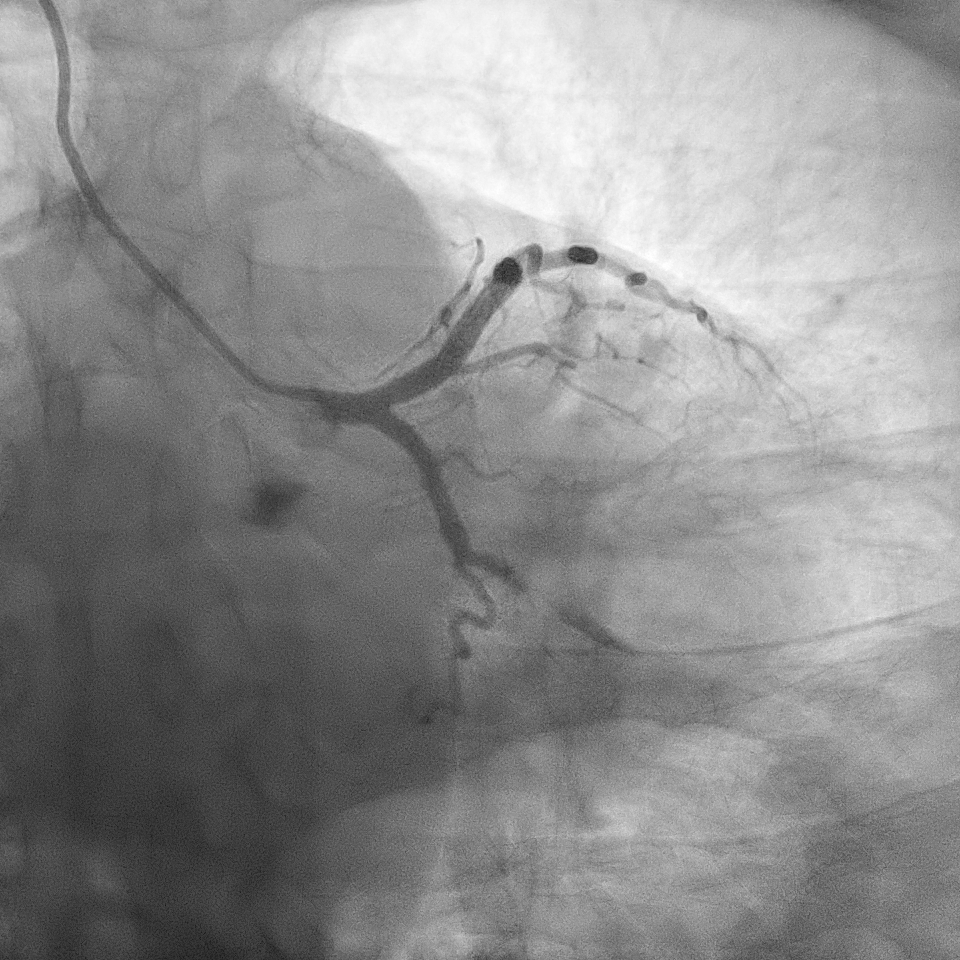

The angiogram showed right dominant system. The left main coronary artery was normal. The left anterior descending (LAD) stent was patent. There was a severe discrete stenosis at obtuse marginal branch (OM1). There was severe stenosis at mid right coronary artery (RCA) and moderate stenosis at proximal RCA.

A right radial artery approach with 6Fr sheath was used. The right coronary system was engaged with 6Fr Judkin Right (JR4) guiding catheter. The posterior left ventricular branch was wired with Runthrough NS. Intravascular ultrasound (IVUS) showed distal RCA landing zone vessel size of 4.0-4.5mm in diameter. The mid RCA showed minimal luminal area (MLA) of 1.95mm2 with fibrous plaque and calcification at 12 o'clock. The proximal RCA landing vessel size was 4.5-5.0mm in diameter. The lesion was predilated with NC Trek Neo balloon 3.0x15mm. Attempted multiple times to deliver the stent SYNERGY 4.0X48mm but failed. The stent could not be passed into proximal RCA and eventually the distal stent edge crimpled and unable to be withdrawn into the guiding catheter. Tried to pull back system enbloc into the radial artery. Attempted to pull the stent into guider but failed again. The guiding catheter was removed. The stent was left with coronary wire in situ. Exchanged 6Fr radial sheath to slender sheath and attempted to snare stent with 2.0mm snare but failed. Attempted multiple wire wrapping technique with 3 BMW wires but failed. Decided to puncture right femoral artery with 8Fr sheath. A 7Fr JR4 guiding catheter was introduced into right brachial artery. A 7mm snare then snared the stent and removed it via femoral. The lesion was predilated with Scoreflex 3.5x20mm, stented with Supraflex Cruz 4.0x48mm and post-dilated with NC balloon 4.5mm. Result was TIMI 3 and no dissection.